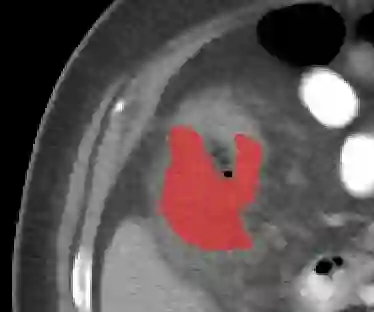

In this paper, we present PRISM, a Promptable and Robust Interactive Segmentation Model, aiming for precise segmentation of 3D medical images. PRISM accepts various visual inputs, including points, boxes, and scribbles as sparse prompts, as well as masks as dense prompts. Specifically, PRISM is designed with four principles to achieve robustness: (1) Iterative learning. The model produces segmentations by using visual prompts from previous iterations to achieve progressive improvement. (2) Confidence learning. PRISM employs multiple segmentation heads per input image, each generating a continuous map and a confidence score to optimize predictions. (3) Corrective learning. Following each segmentation iteration, PRISM employs a shallow corrective refinement network to reassign mislabeled voxels. (4) Hybrid design. PRISM integrates hybrid encoders to better capture both the local and global information. Comprehensive validation of PRISM is conducted using four public datasets for tumor segmentation in the colon, pancreas, liver, and kidney, highlighting challenges caused by anatomical variations and ambiguous boundaries in accurate tumor identification. Compared to state-of-the-art methods, both with and without prompt engineering, PRISM significantly improves performance, achieving results that are close to human levels. The code is publicly available at https://github.com/MedICL-VU/PRISM.